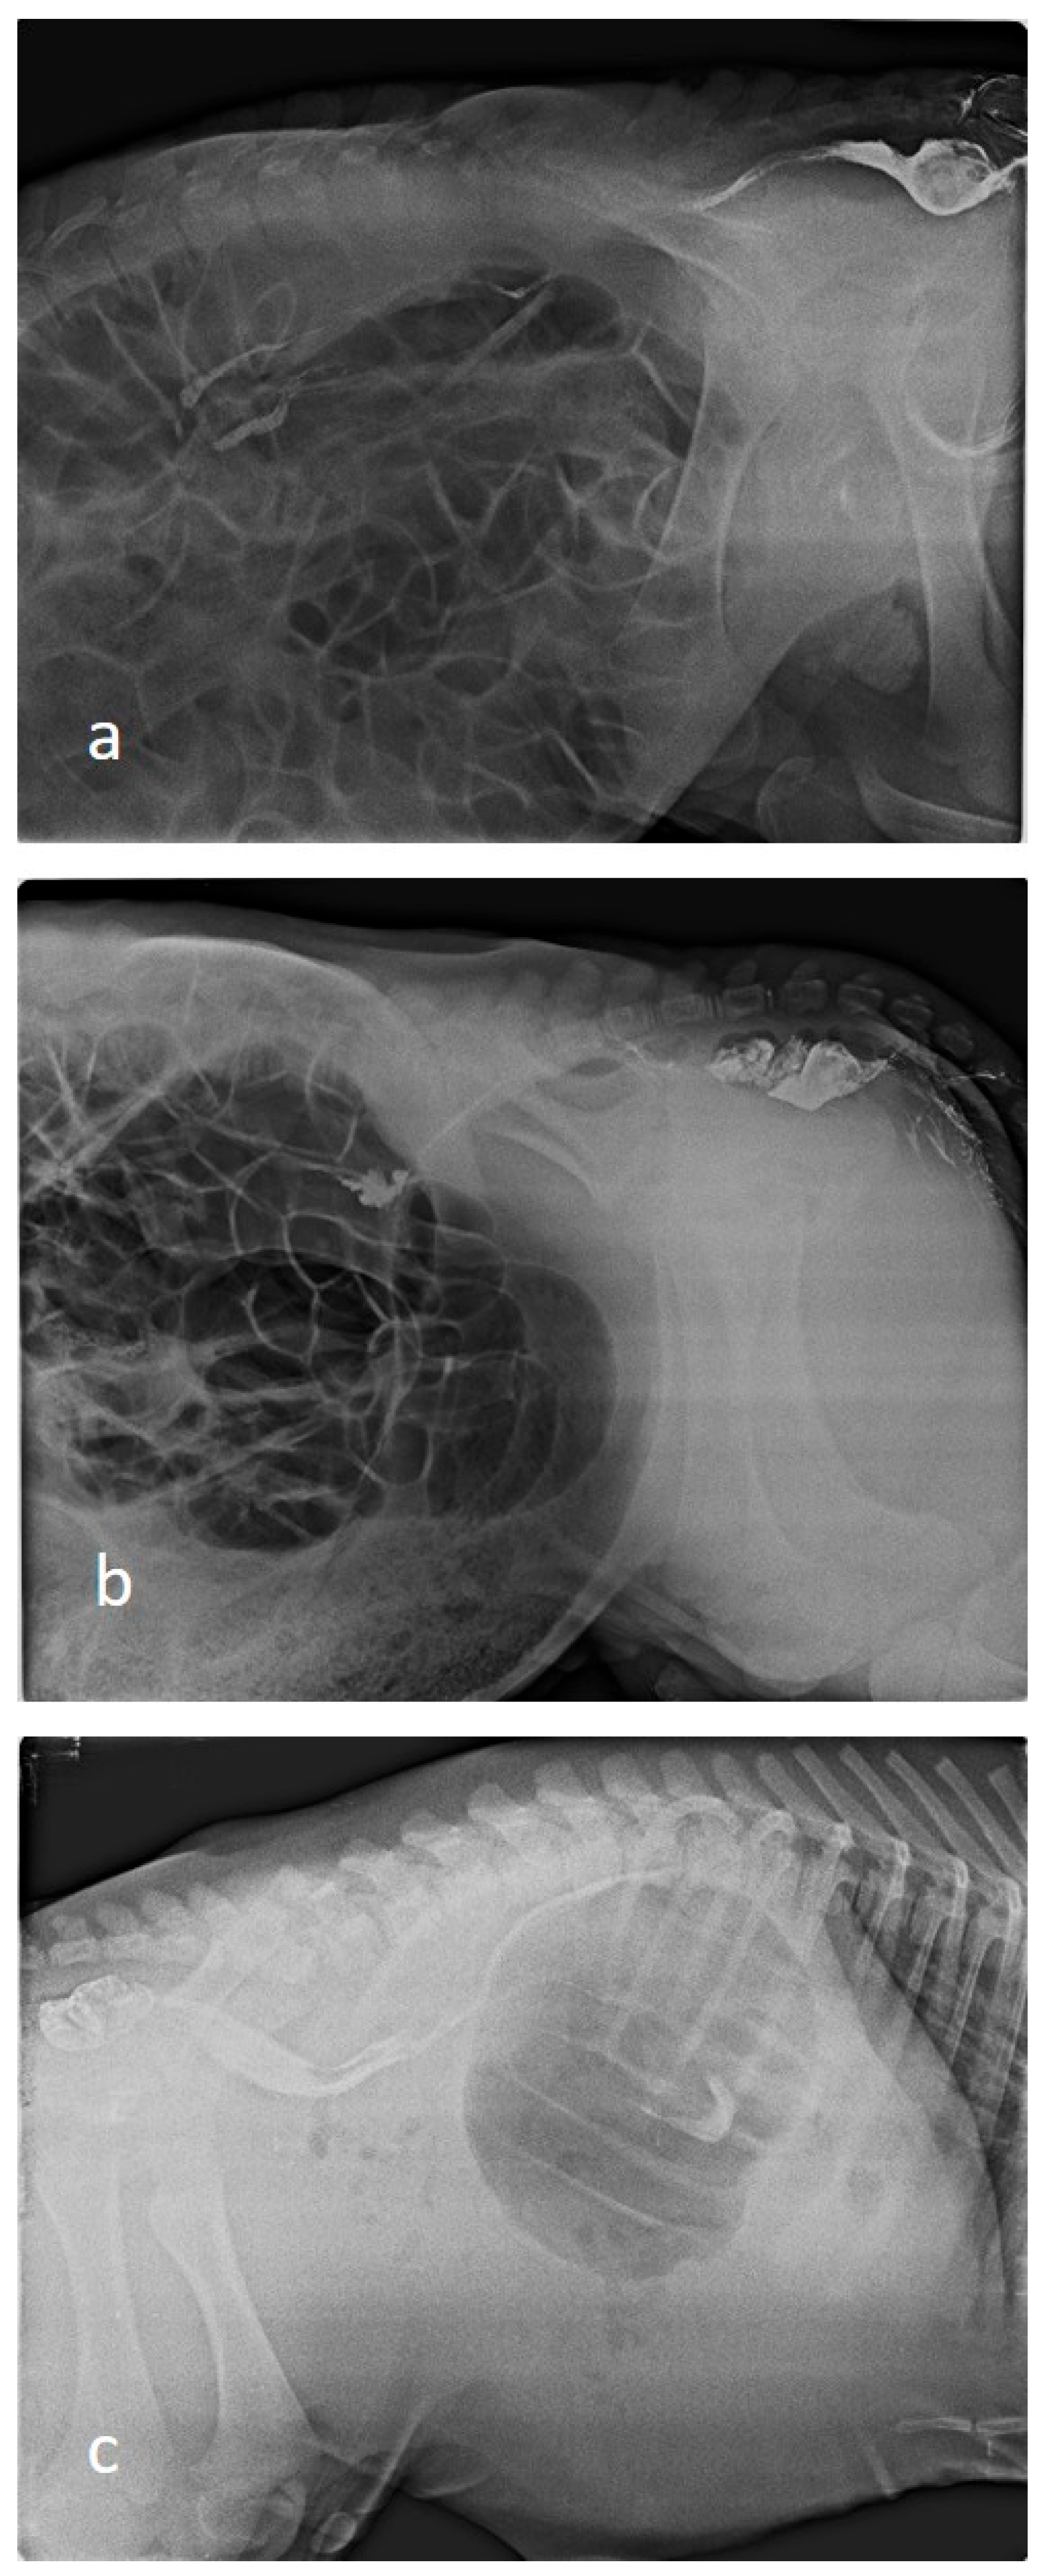

2.7. Diagnostic Imaging

Indirect radiography was performed in all calves by rectal administration of barium sulphate contrast agent. Barium sulphate (E-Z-HD Barium sulphate, 98% powder, 340 g, OPAKIM, İstanbul, Türkiye) was diluted 1:3 with water and administered at a dose of 1 mL/kg via rectal probe [30]. The blind ends of the colon or rectum were radiographically visualised after barium administration (Figure 1). Barium-contrast radiography also showed the blind part of the colon. Indirect radiography was performed in the latero-lateral position using a 70 kilovolt (kV) and 150 milliampere (mA) setting on an X-ray machine (BLD-150AJ, AJEX Meditech Ltd., Seoul, Republic of Korea) with Fujifilm Computed Radiography (CR-IR 392, Fujifilm, Shanghai, China).

Figure 1.

Indirect radiographic images of calves ((a); Type I, (b,c); Type III).

3.4. Radiographic Findings

In cases of atresia coli, radiographic evaluation revealed that the intestinal passage terminated in a distal segment, resulting in severe proximal distension. In abdominal radiographs of calves, it was observed that the spiral colon and cecum were markedly distended with gas and liquid content, whereas distal colonic segments were free of gas and content. An enlarged gas-filled intestinal anus, especially in the left flank region, was typical. Contrast-enhanced radiography revealed that the contrast had travelled up to a certain level, and no passage distal to the atretic segment was observed.